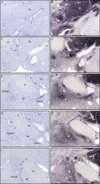

Figure 2: The rostral (top) and more caudal (bottom) human nucleus subputaminalis (NSP), from case N5 stained for Nissl substance (left) and choline acetyltransferase (right). Arrowheads denote NSP neurons. Note, in more rostral sections, the NSP is localized ventral to the putamen, in one or several clusters. At the intermediate level, the NSP is predominantly found lateral to the posterior limb of the anterior commissure and medial to the putamen. More caudally, as the anterior commissure recedes, NSP neurons are located dorsal to the posterior limb of the anterior commissure, medioventral to the putamen. Scale bar = 1 mm. Abbreviations: ac, anterior commissure; ap, ansa peduncularis; Ch4(id), interomediodorsal-Ch4; Ch4(iv), interomedioventral-Ch4; Pu, putamen.

All cholinergic cells ventral to the basal ganglia and anterior commissure and medial to the putamen were labeled and counted as the NBM (Figure 1). Differentiation of cells of the NSP from cells of the rest of the NBM was based on location of the neurons, with NSP neurons seen in aggregated clusters near the ventral border of the putamen (Figure 2), according to criteria described previously.Reference Simić, Mrzljak, Fucić, Winblad, Lovrić and Kostović16 Nissl staining allowed for the visualization of large, hyperchromatic neurons of various morphologies, including multipolar, spindle-shaped, and fusiform, belonging to the NSP. Rostrally, at the level of the decussation of the anterior commissure, NSP neurons could be seen at the ventrolateral border of the putamen (Figure 2). At the intermediate level, the NSP was lateral to the posterior limb of the anterior commissure and was medial as well as ventral to the putamen (Figure 2). Caudally, the NSP was ventral to the putamen and dorsolateral to the posterior limb of the anterior commissure, which had regressed (Figure 2). The cell population was delineated from the rostral–caudal extent using the decussation of the anterior commissure as the rostral landmark, and mammillary bodies as the caudal limit (Figure 1). All Ch4 sectors apart from NSP were considered as NBM for the purposes of our analyses.